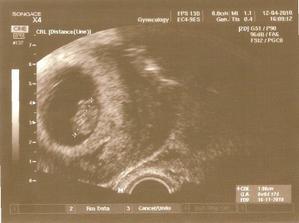

12.4. první těhuporadna, 9tt, mimi má necelé 2 cm, vše je v pořádku (ťuk ťuk ťuk), zatím vypadá spíš jako měňavka